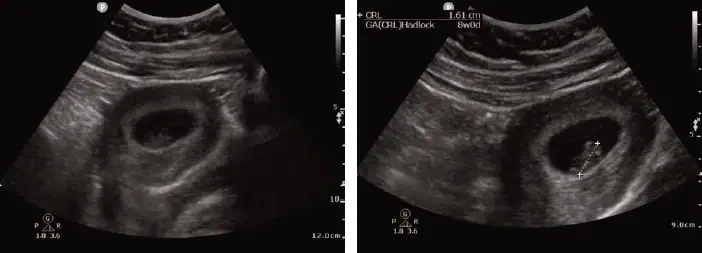

A 28-year-old female presents to urgent care with mild left lower quadrant (LLQ) abdominal pain that began earlier in the day. The discomfort is dull, intermittent, and non-radiating. She denies vaginal bleeding, fever, nausea, vomiting, or urinary symptoms. Her last menstrual period was approximately 2 months ago, although she reports a history of irregular cycles.

She appears well and is hemodynamically stable. An abdominal exam reveals mild LLQ tenderness without rebound or guarding. A pelvic exam shows no discharge, bleeding, adnexal tenderness, or cervical motion tenderness. No masses are appreciated. A urine pregnancy test performed in the clinic returns positive. Given concern for ectopic pregnancy, a transabdominal point-of-care ultrasound (POCUS) is performed.

View the images above and consider the likely diagnosis and next steps. The resolution of the case is described on the following page.